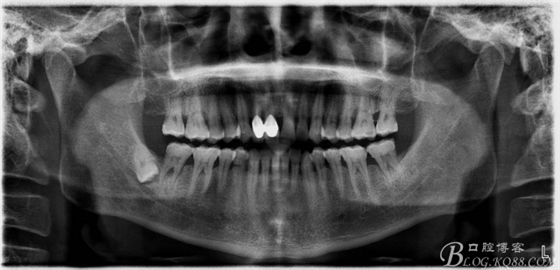

48未萌出,47遠(yuǎn)中可探及深約7mm的牙周袋。頰側(cè)47、48之間牙齦紅腫,有少量血性滲出。X線根尖片顯示:48牙冠反轉(zhuǎn)倒置,47遠(yuǎn)中牙槽骨吸收明顯。CBCT顯示:48牙冠近中面位于下頜管內(nèi)。

一、術(shù)前全景片影像: